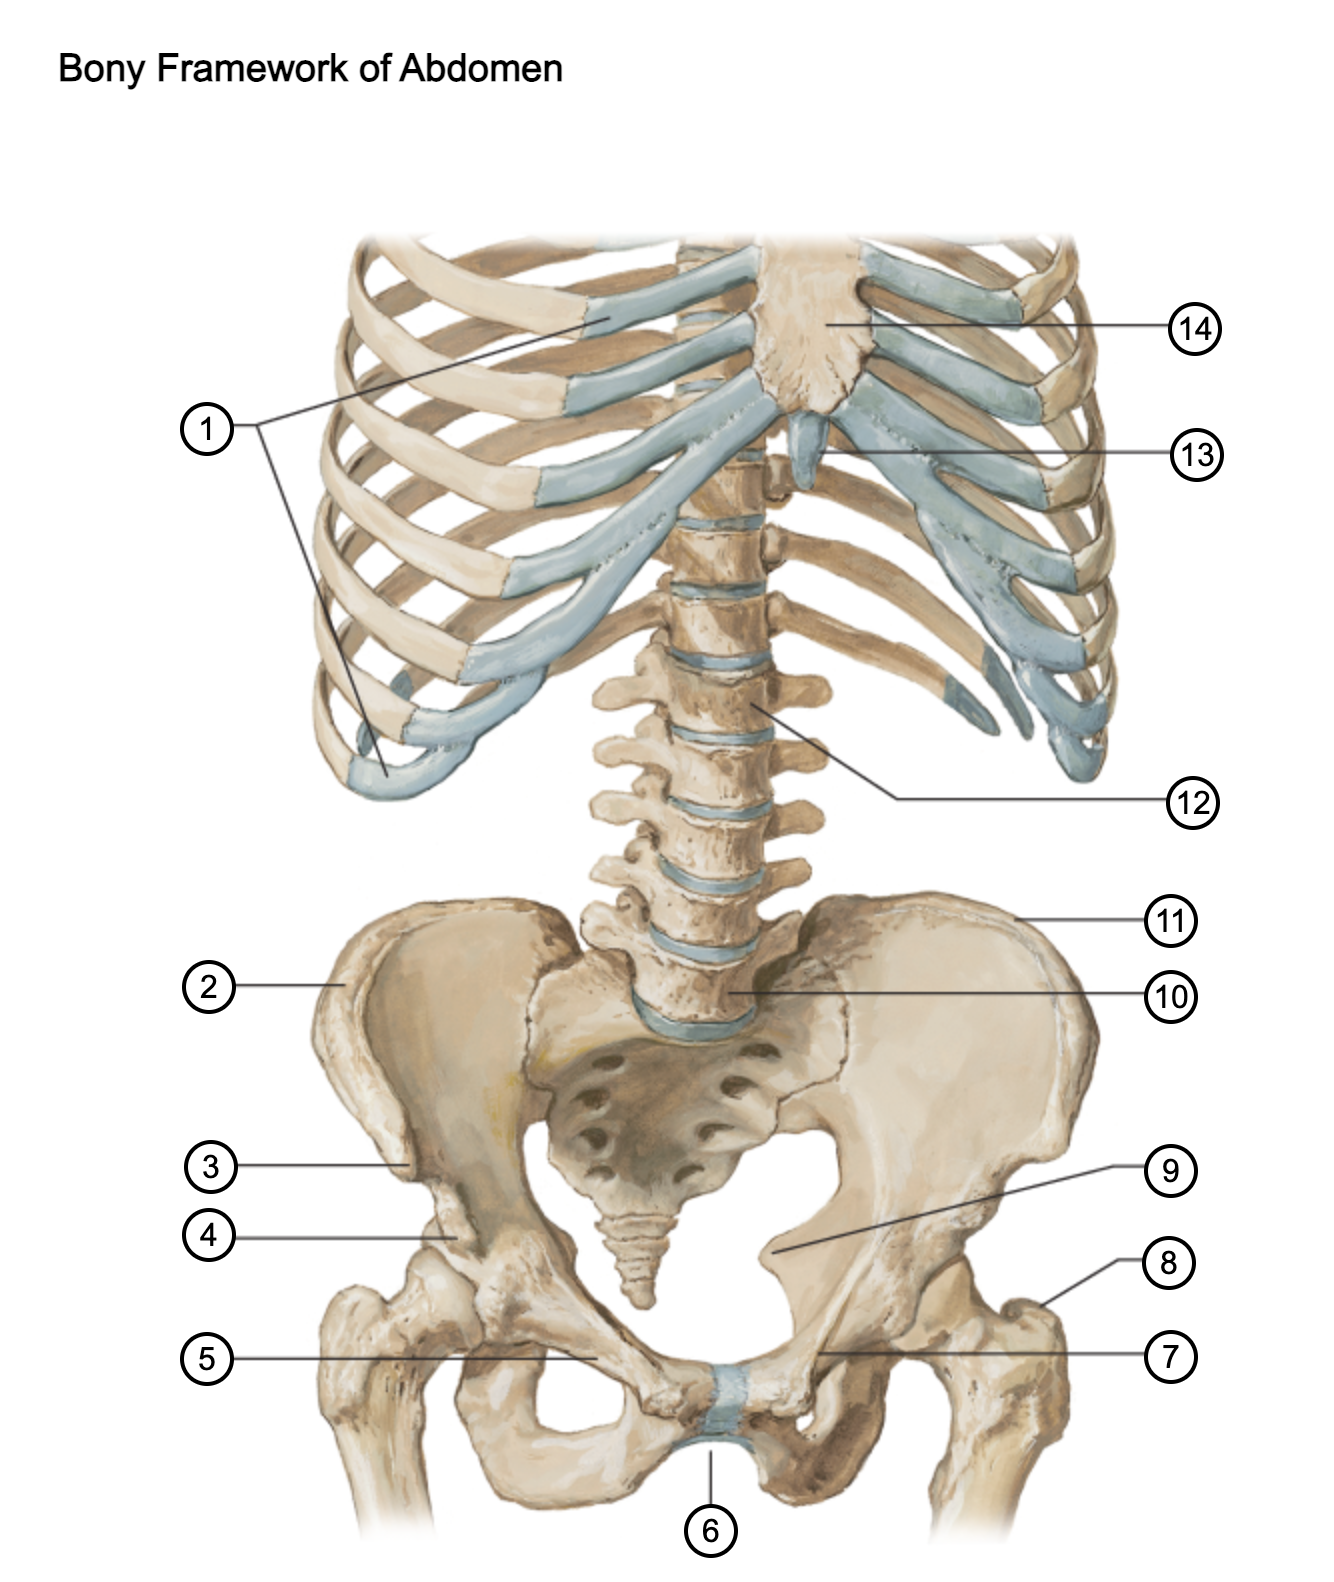

1

costal cartilages

2

iliac crest

3

anterior superior iliac spine

4

anterior inferior iliac spine

5

superior pubic ramus

6

pubic arch

7

pecten pubis

8

greater trochanter

9

ischial spine

10

L5 vertebra

11

iliac crest

12

L1 vertebra

13

xiphoid process

14

body of sternum